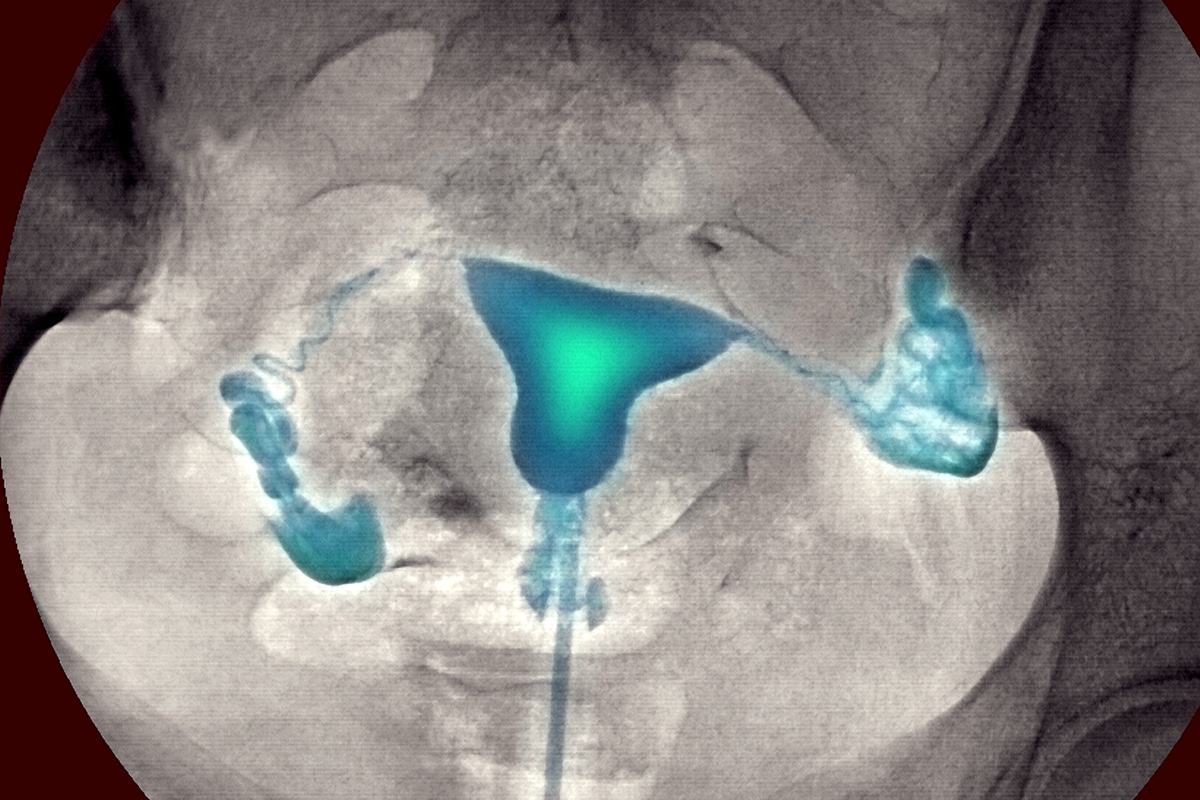

عکس رنگی رحم؛ هیستروسالپنگوگرافی (HSG) شکل رحم را ارزیابی می کند و باز بودن لوله های فالوپ را بررسی می کند. همچنین برای بررسی سقط جنین به دلیل مشکلات در رحم استفاده می شود.

HSG یک آزمایش اشعه ایکس از رحم و لوله های فالوپ است. در این روش از نوع خاصی از اشعه ایکس به نام فلوروسکوپی و ماده حاجب استفاده می شود.

پزشک از فلوروسکوپی استفاده می کند تا اندام های داخلی شما را در حال حرکت ببیند. پزشک یا تکنسین شما رحم و لوله های فالوپ را با ماده حاجب محلول در آب پر می کند. سپس رادیولوژیست شما از فلوروسکوپی برای مشاهده و ارزیابی آنها استفاده می کند.

هیستروسالپنگوگرام (HSG) یک آزمایش با اشعه ایکس است که به داخل رحم و لوله های فالوپ وهمچنین ناحیه های اطراف آنها نگاه می کند. در صورتی که برای باردار شدن با مشکل مواجه هستید یا دچار ناباروری باشید ممکن است انجام شود. همچنین به تشخیص بسیاری از مشکلات از جمله خونریزی غیرقابل توضیح واژینال، ناباروری و سقط های مکرر کمک می کند.این آزمایش بسیار شبیه معاینه زنان انجام می شود. این آزمایش هیچ اثر مضر شناخته شده ای ندارد و تصویر واضحی از بافت های نرم که در اشعه ایکس به خوبی نشان داده نمی شوند، ارائه می دهد.

در طول آزمایش، یک رنگ که یک ماده کنتراست در یک لوله نازک قرار می گیرد. این لوله از طریق واژن فرد وارد رحم آن می شود. از آنجایی که رحم و لوله های فالوپ به یک دیگر متصل هستند، رنگ به داخل لوله های فالوپ هم جریان می یابد. تصاویر با استفاده از پرتو ثابت اشعه ایکس یا همان فلوروسکوپی در حین عبور رنگ از قسمت های رحم و لوله های فالوپ گرفته می شود. تصاویر می توانند مشکلاتی مثل آسیب یا ساختار غیر طبیعی رحم و یا لوله های فالوپ را نشان دهند. آنها حتی می توانند انسدادی را نشان دهند که از حرکت تخمک از طریق لوله های فالوپ به سمت رحم جلوگیری می کند. همچنین می تواند از حرکت اسپرم به لوله فالوپ و پیوستن به لقاح با تخمک جلوگیری کند. این آزمایش ممکن است مشکلاتی را در داخل رحم پیدا کند که بر باروری تأثیر می گذارد.